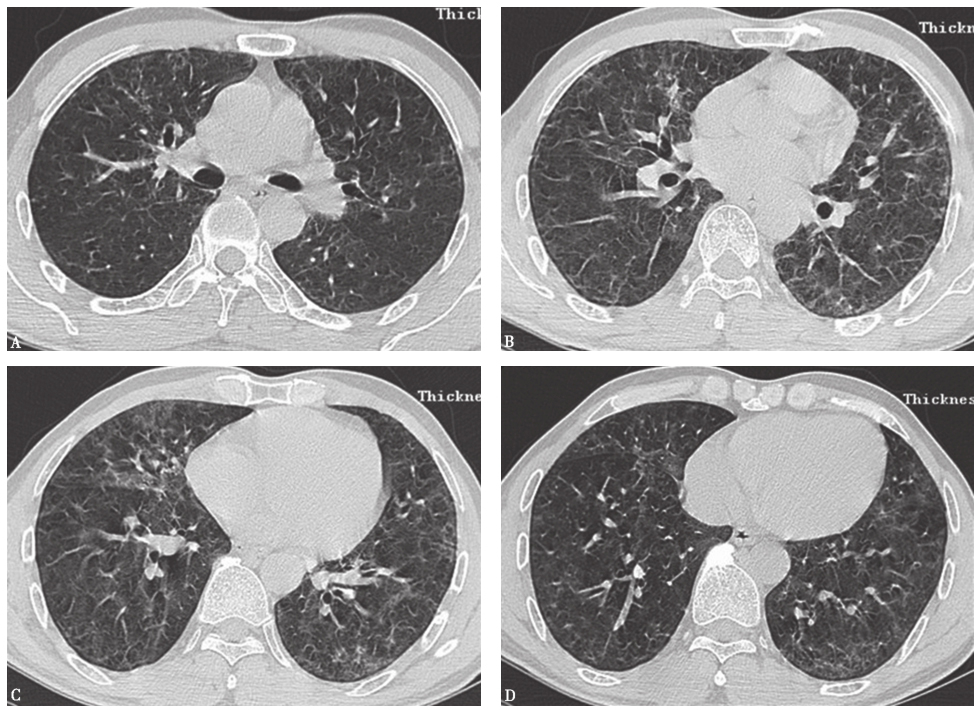

患者经泼尼松(20mg,每天2次)口服治疗,并且脱离原有工作环境,1个月后复查胸部HRCT示两肺磨玻璃影及小结节影较前进一步吸收(图17),咳嗽、气喘症状明显缓解。

图17泼尼松治疗1个月后胸部HRCT表现

HRCT显示磨玻璃影及小结节影进一步减少,双肺胸膜下少量小结节影

两肺散在磨玻璃影及小结节影(图13),局部网状影,较入院前(图1)明显吸收、好转。

图13入院后胸部HRCT表现

患者入院后所做系列检查显示:①自身抗体均阴性,结合临床表现,基本可排除风湿免疫病;②常规病原学检查均阴性;③胸部HRCT可见两肺小结节影、磨玻璃影,较外院CT明显吸收、好转,证明外院激素治疗有效。此外,患者在未接受抗肿瘤治疗的情况下小结节影吸收、好转,与肺转移癌不符(由于癌细胞不断增殖,粟粒状癌灶可在短时间内渐进性增大)。